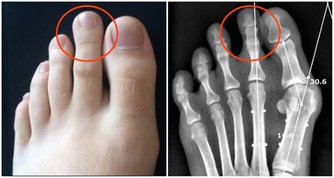

4、骨骼強壯中醫認為,腎主骨,骨靠腎精滋養,腎好骨才好。

腎氣衰敗會出現骨質疏鬆、腰酸背痛,甚至牙齒出現鬆動。